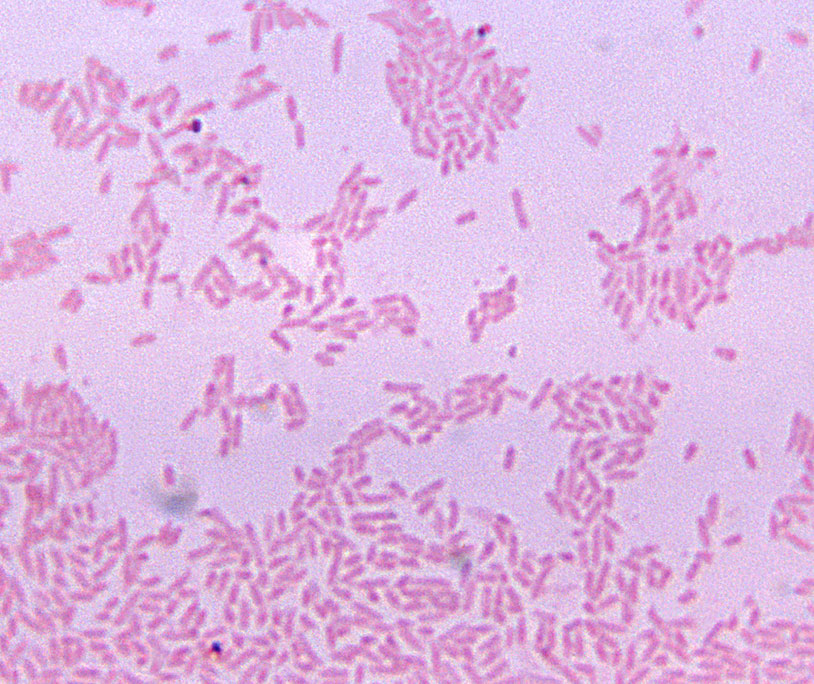

gram negative bacilli

Your Gram stain is complete and correct. Which of the following statements would apply to the image you see?

unknown is negative, as S.aureus is known positive, so it can be ruled out

One initial suspect bacteria you considered was the common sepsis (bloodstream infection) organism Staphylococcus aureus. Why can we rule this organism out as the cause in the patient?

gram positive cocci

Your Gram stain is complete and correct. Which of the following would apply to the image you see?

gram stain is positive, suggests streptococci. H influenzae is gram neg/ruled out

One initial suspect bacteria you considered was the common otitis media bacterium Haemophilus influenzae. Why can we rule this organism out as the cause in the patient?